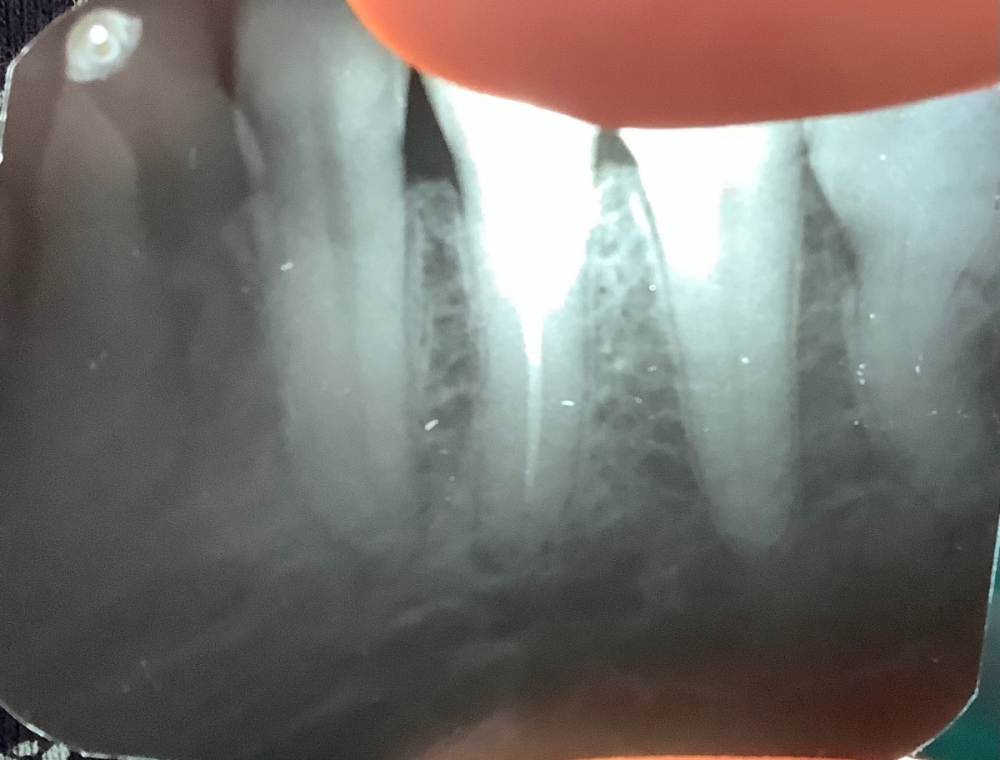

Аристократ2021 Опубликовано 21 мая, 2021 Поделиться Опубликовано 21 мая, 2021 Добрый день уважаемые коллеги! Посмотрите пожалуйста снимок. Пациента беспокоила чувствительность на горячее и незначительные боли. После распломбирования канала зуб ноет, чувствительность на горячее прошла. Какой прогноз? Ссылка на комментарий

Sier10 Опубликовано 1 июня, 2021 Поделиться Опубликовано 1 июня, 2021 (изменено) 21.05.2021 в 14:36, Аристократ2021 сказал: Добрый день уважаемые коллеги! Посмотрите пожалуйста снимок. Пациента беспокоила чувствительность на горячее и незначительные боли. После распломбирования канала зуб ноет, чувствительность на горячее прошла. Какой прогноз? при лечении инфицированных случаев (как и в вашем случае) непосредственно после манипуляции может возникать дискомфорт. Иногда даже полноценное обострение с отёком, смотря как и чем вы проходили каналы Изменено 1 июня, 2021 пользователем Sier10 Ссылка на комментарий